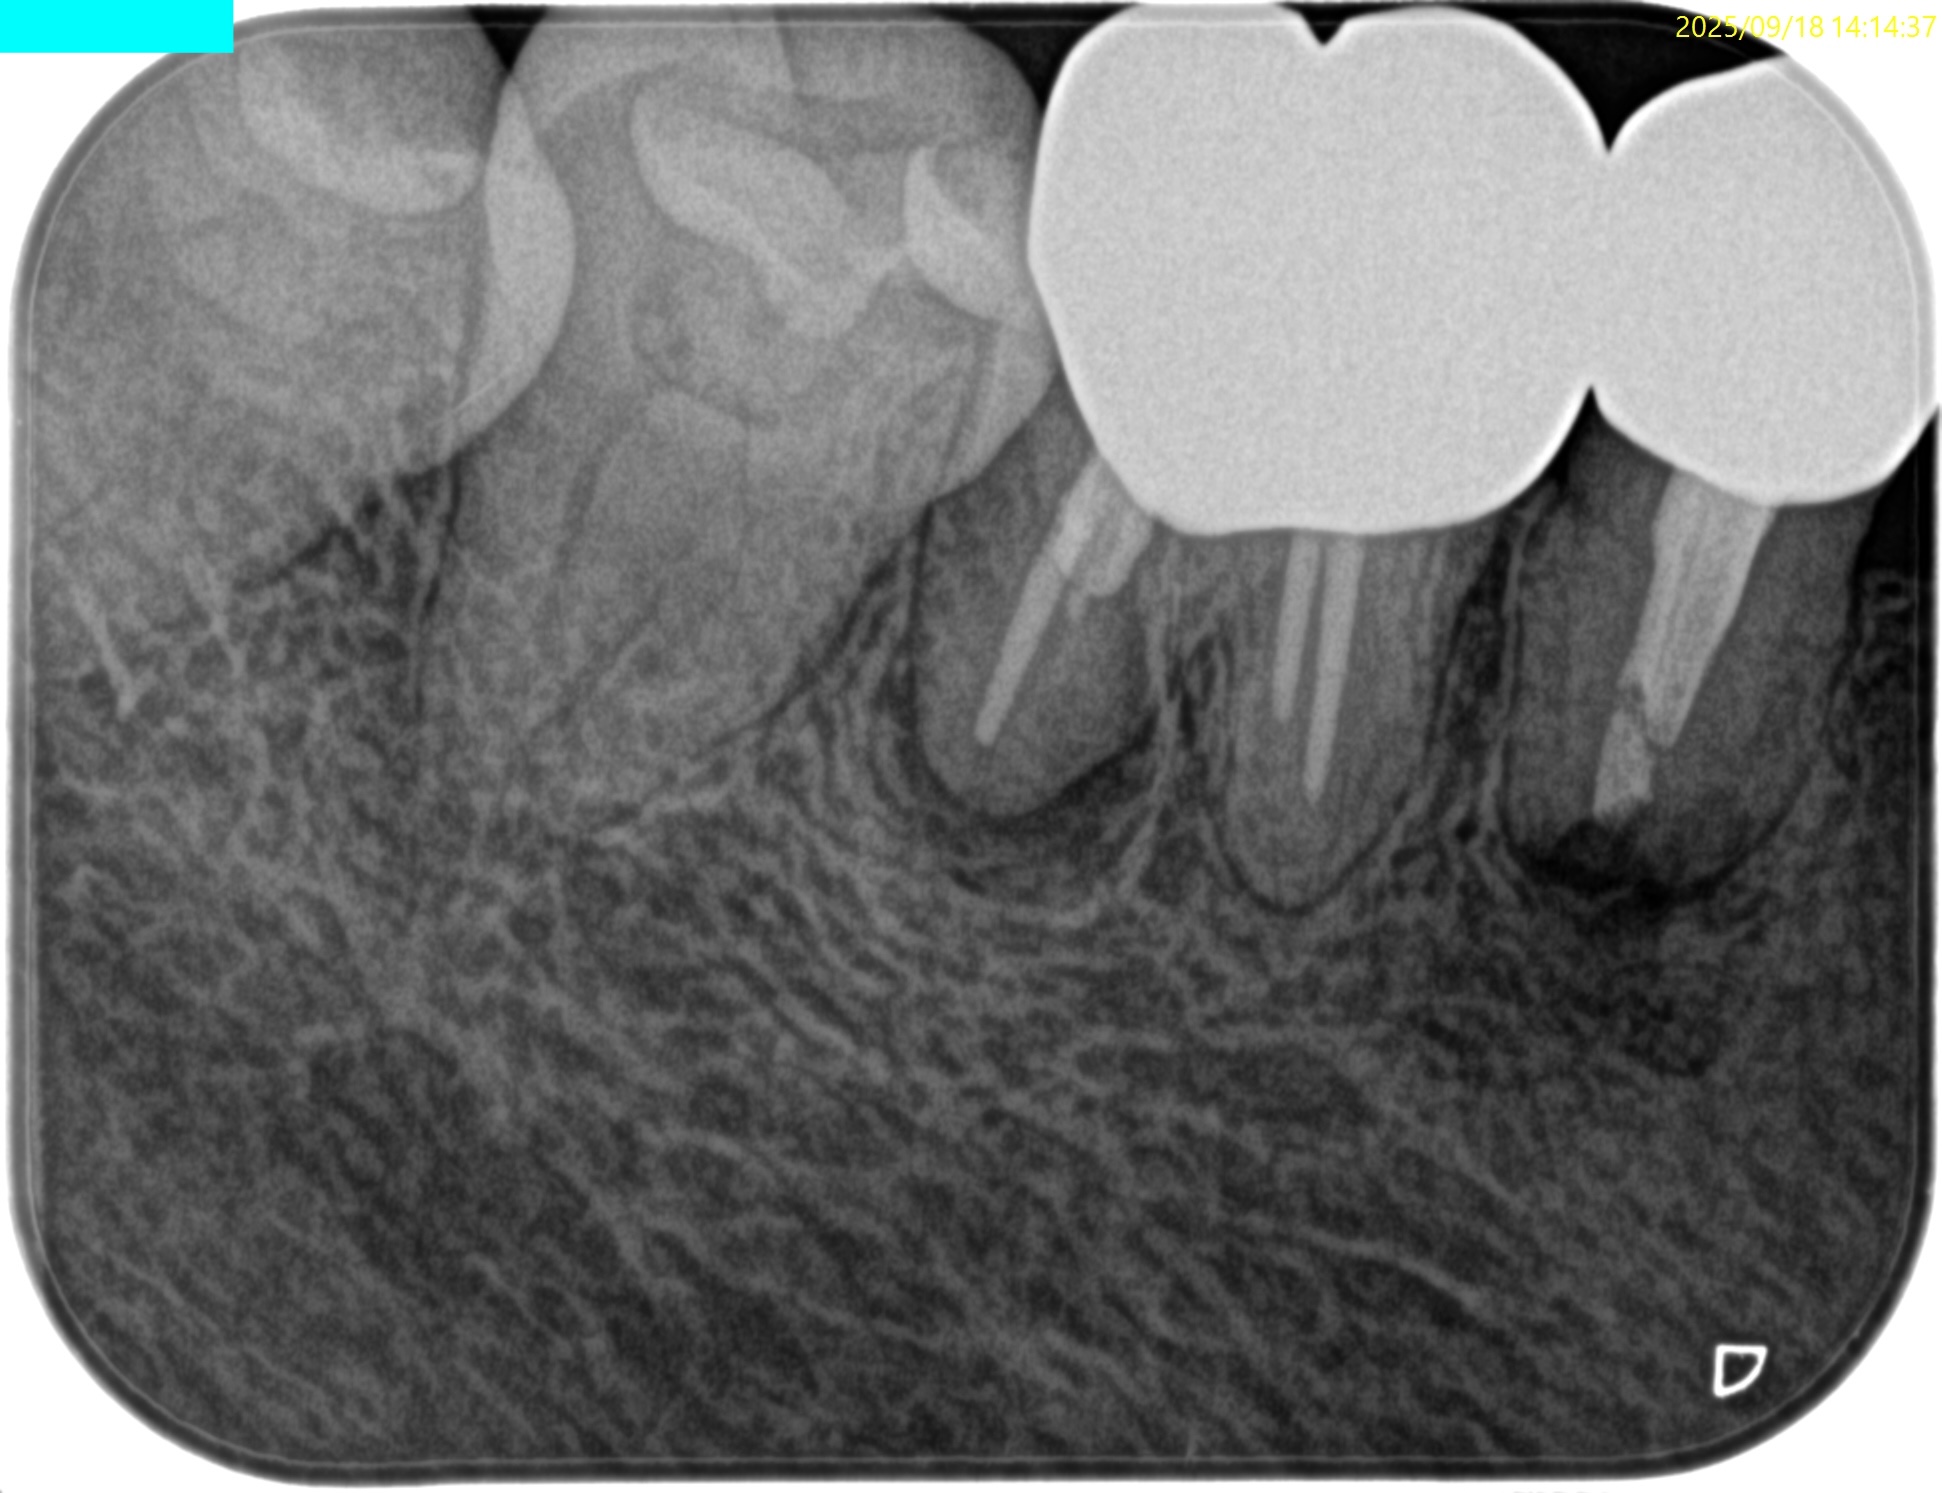

MB

ML

D

PA, CBCTを撮影した。